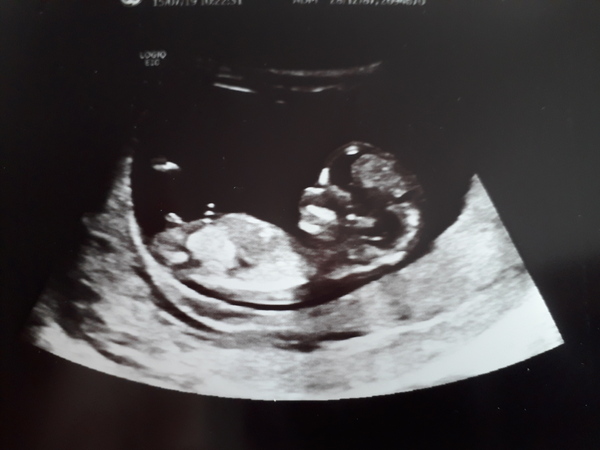

We had our 12 week scan today. Baby is 11+6 and looking very healthy and wriggly. Cheered me up so much after the horrible morning sickness.

What do we think, boy or girl? DH and I think another boy.

Good luck to everyone having their scans today!